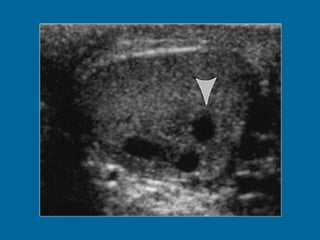

Intratesticular varicocele in a 38-year-old man.  (a) Transverse oblique US scan of left testis reveals multiple intratesticular anechoic cystic areas (arrowhead).  (b) Duplex Doppler US scan shows that venous flow in these cystic areas increases during a Valsalva maneuver (arrowhead).

Intratesticular varicocele ina 38-year-old man. (a) Transverse oblique US scan of left testis reveals multiple intratesticular anechoic cystic areas (arrowhead). (b) Duplex Doppler US scan shows that venous flow in these cystic areas increases during a Valsalva maneuver (arrowhead).